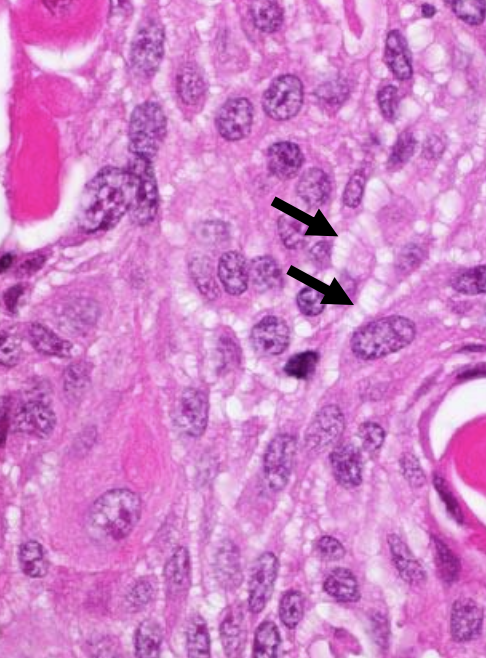

Morphology

This tumour arises from neuroendocine cells in the bronchial epithelial lining. It has no precursor lesions. The tumour cells are small with little cytoplasm, but darks hyperchromatic nuclei with finely granular chromatin. Additionally nuclear moulding is present, where the nucleus mould to cell shape